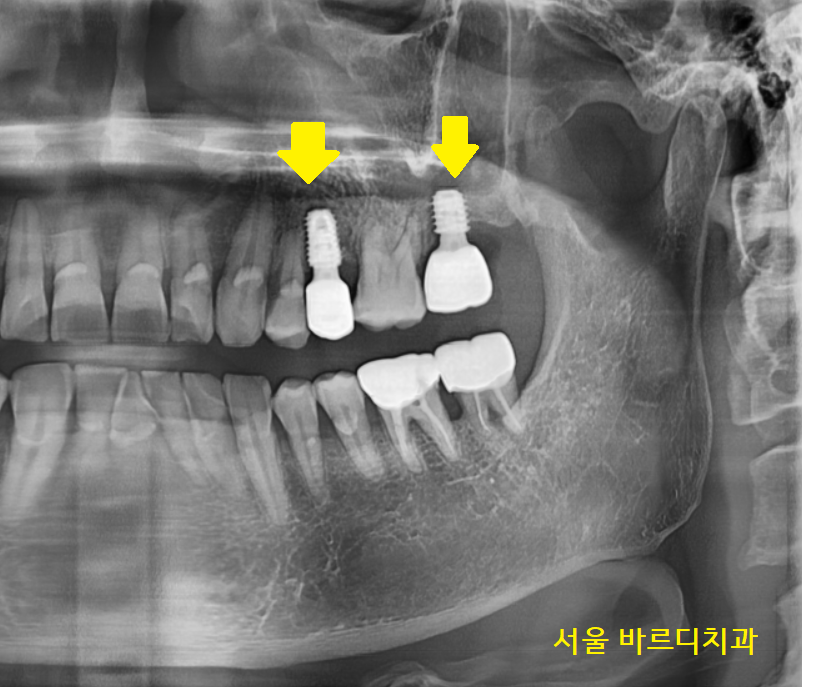

23.12.29

사진을 보시더라도

옆에 치아보다

임플란트 길이가 짧은 게 보이시죠?

시간이 흘러 임플란트와 내 뼈가 잘 붙어서

보철을 만들어드렸습니다.